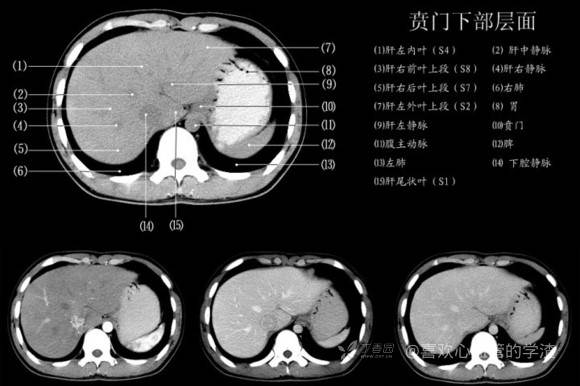

其实你离掌握上腹部 CT 影像只有一套高清实用图谱的距离,下面把我最喜欢的这本图谱分享给大家,为了方便阅读,我加了中文标识。后面附赠几张血管相对位置解剖关系图片,帮助大家理解(文中多图,建议在 wifi 环境下查看)。